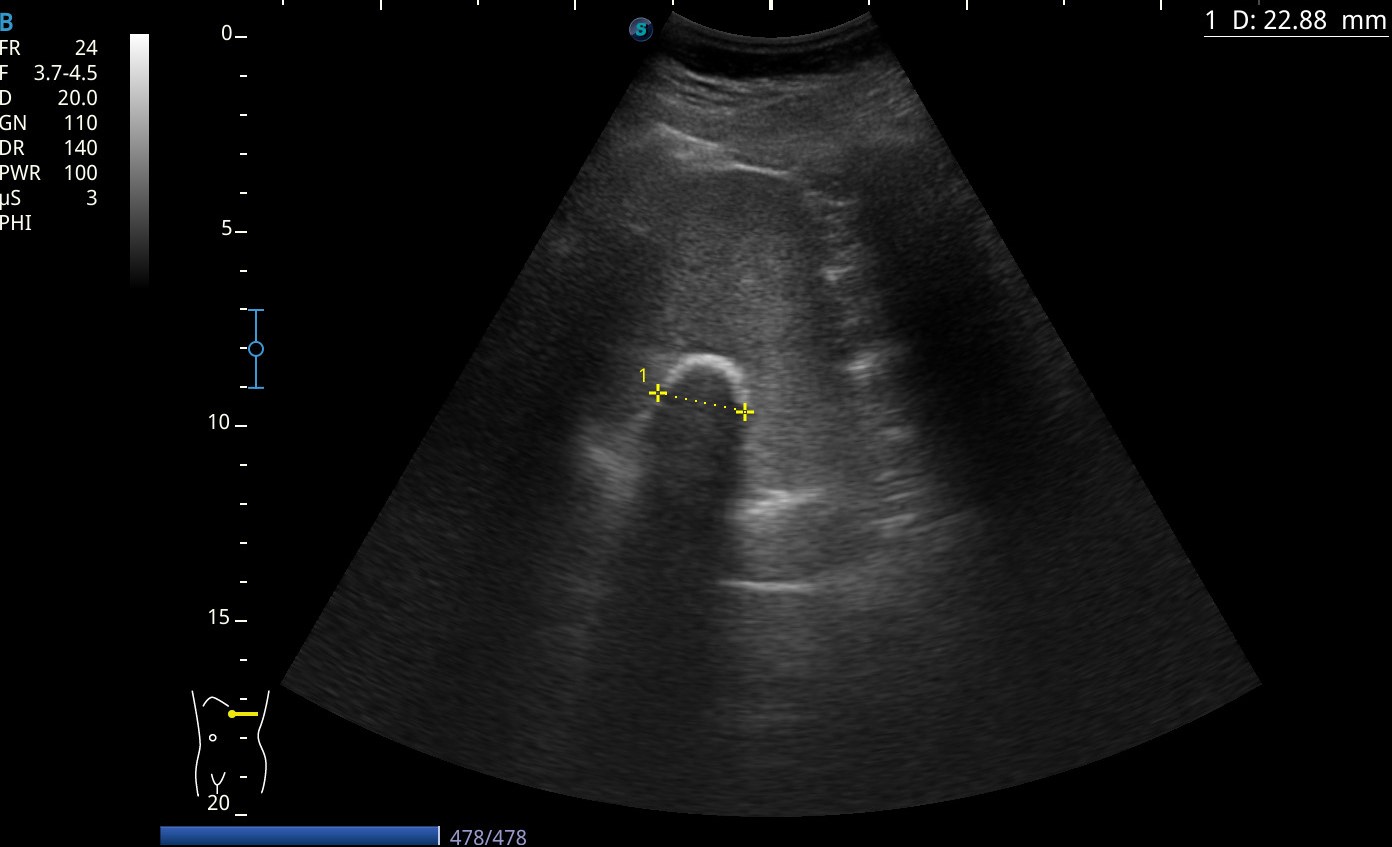

Hallazgos ecográficos

En la ecografía se visualiza una masa calcificada en bazo.

Se amplía estudio a TC abdominal que confirma el diagnóstico de quiste hidatídico calcificado.